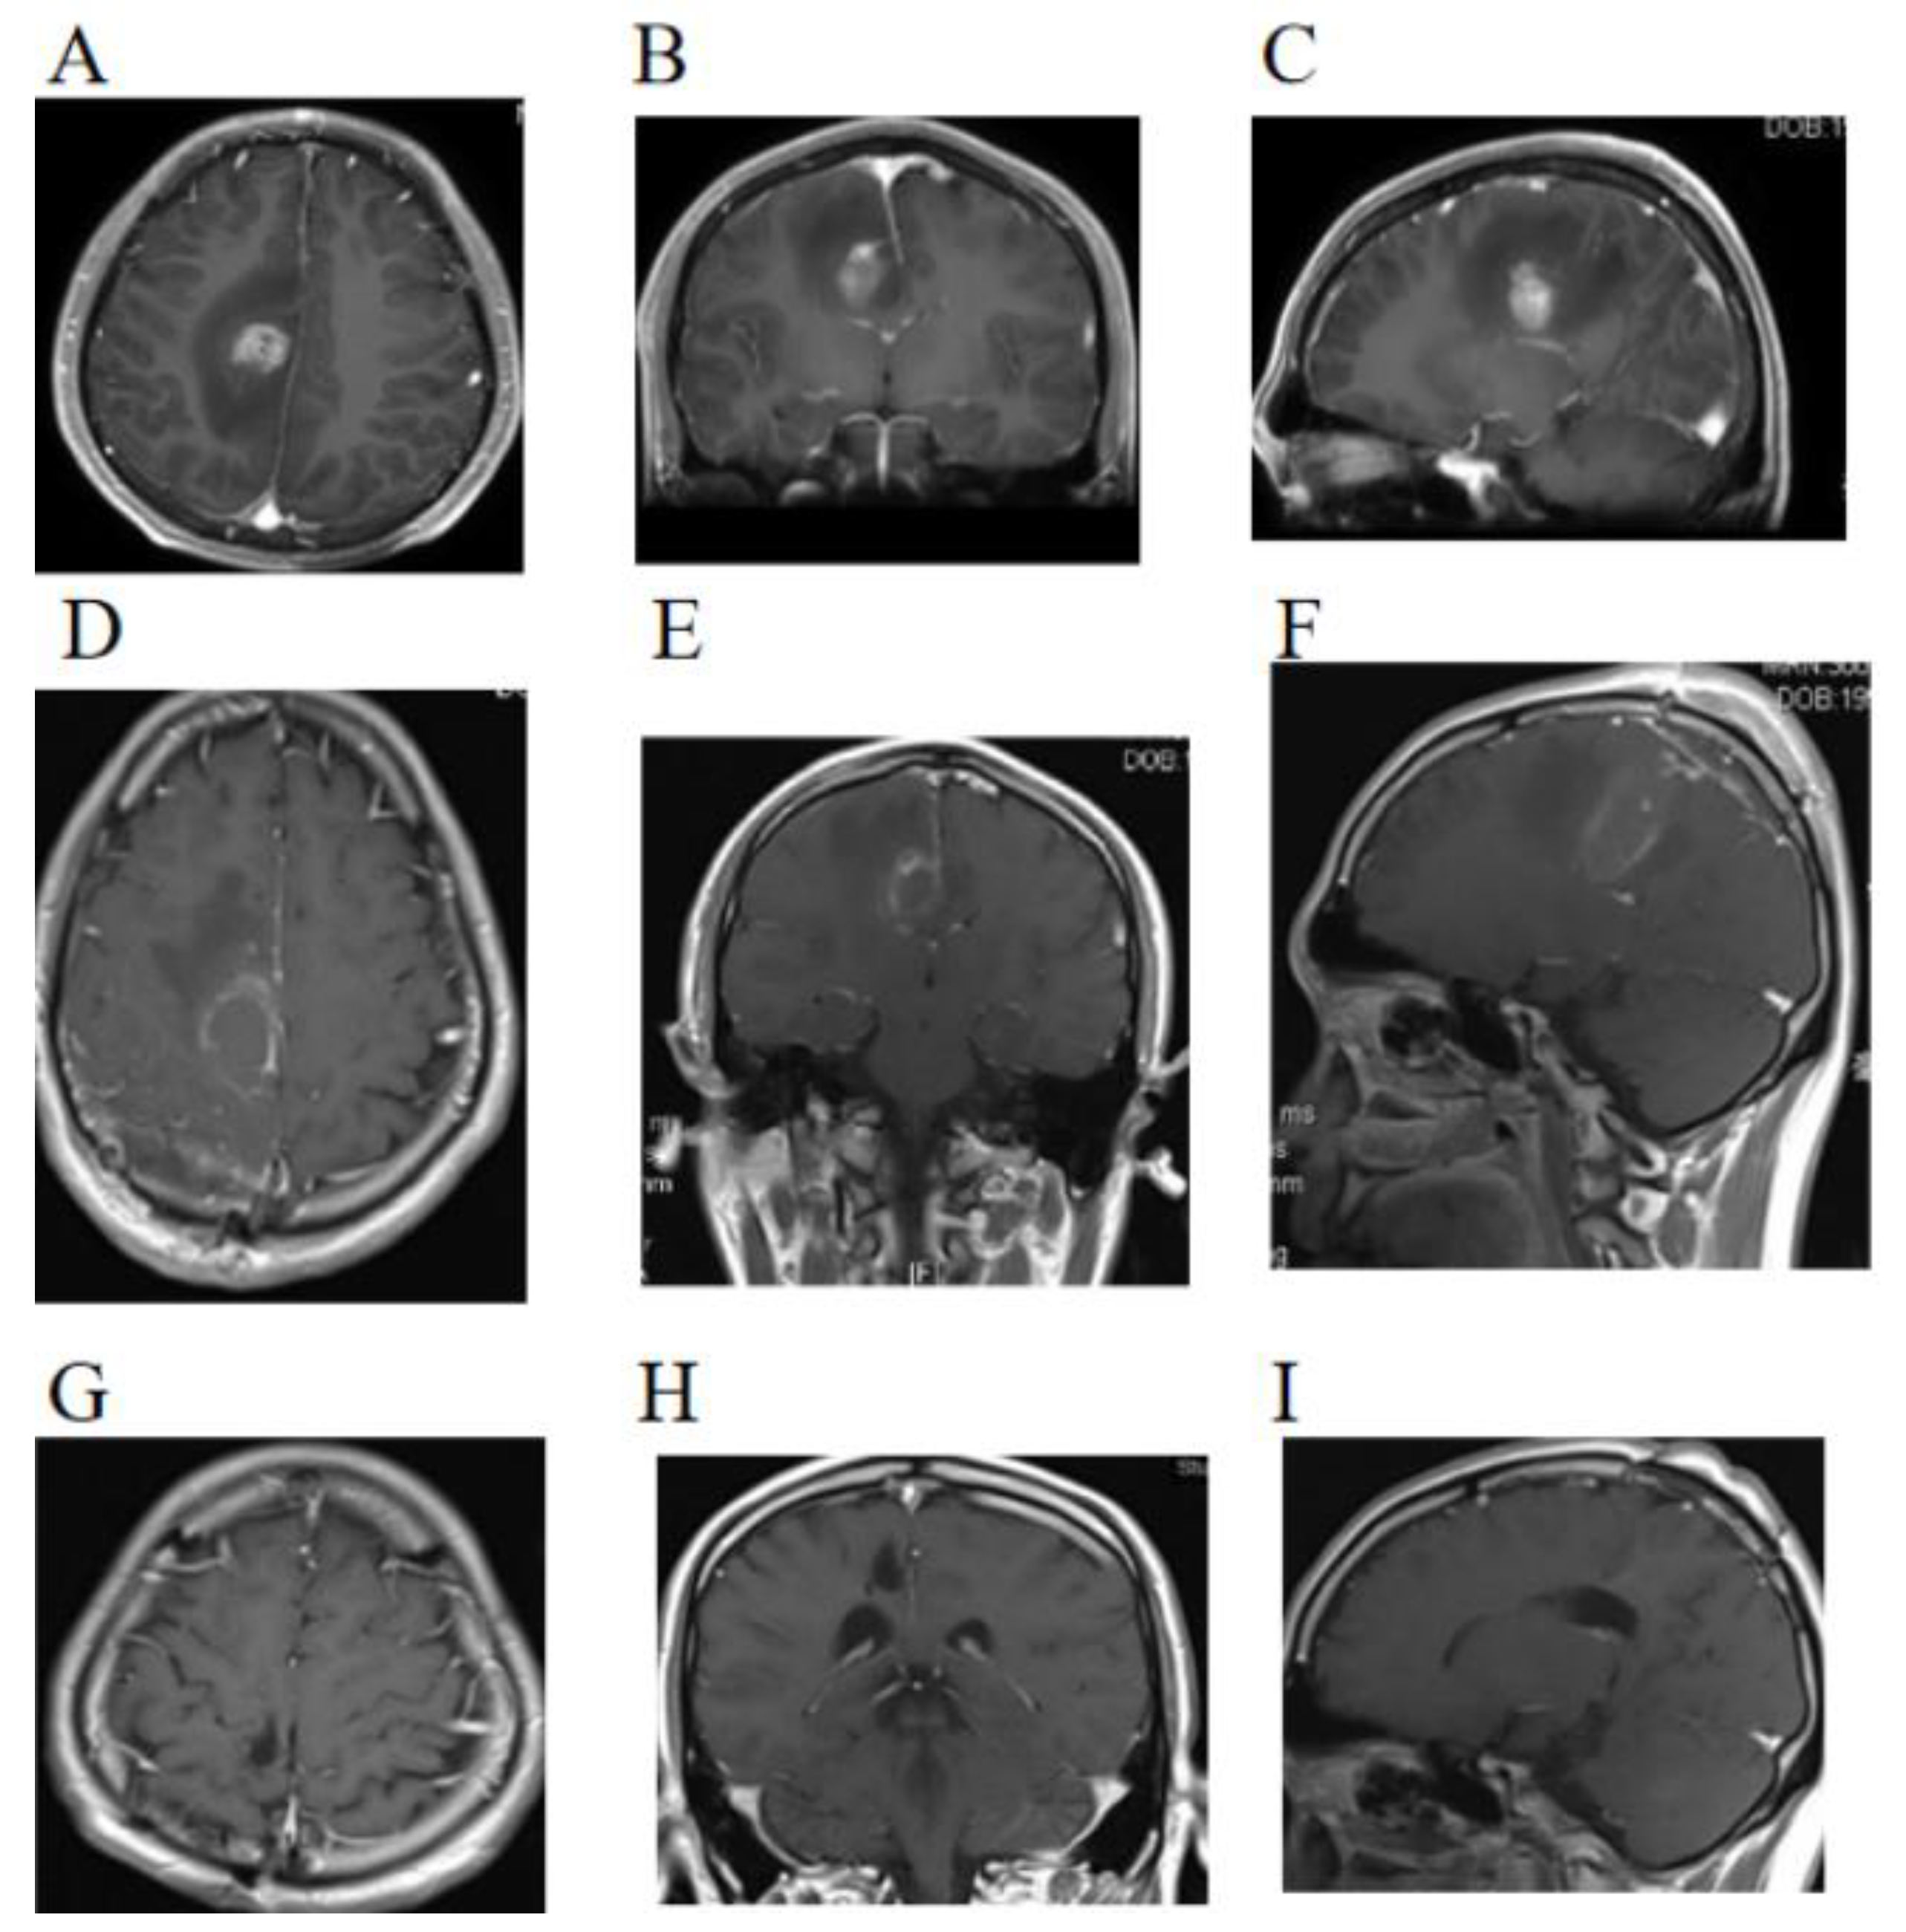

2. Case Presentation